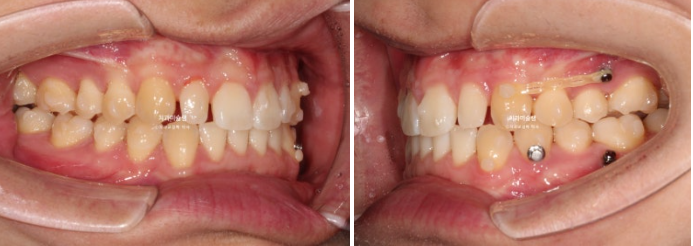

2022년 10월 비대칭으로 내원하신 분입니다.

중심선 불일치, 왜소치로 인한 벌어짐, 송곳니 덧니 등이 보입니다.

환자분이 비대칭으로 느끼는 가장 큰 이유는

한쪽 얼굴이 더 크다.

위 치아 중심선이 인중과 어긋나 있다

두가지 입니다.

이 환자분이 한쪽으로만 씹었던 이유는 반대쪽에 가위교합이 있었기 때문입니다.

파란 화살표가 가위교합이고 위 큰어금니는 바깥으로 나가있고 대합치는 안쪽으로 쓰러지며 가위처럼 서로 엇갈려 교합되는 상태를 말합니다.

파란 화살표 치아가 바깥으로 뻗치면서 가위교합의 원인이 됩니다.